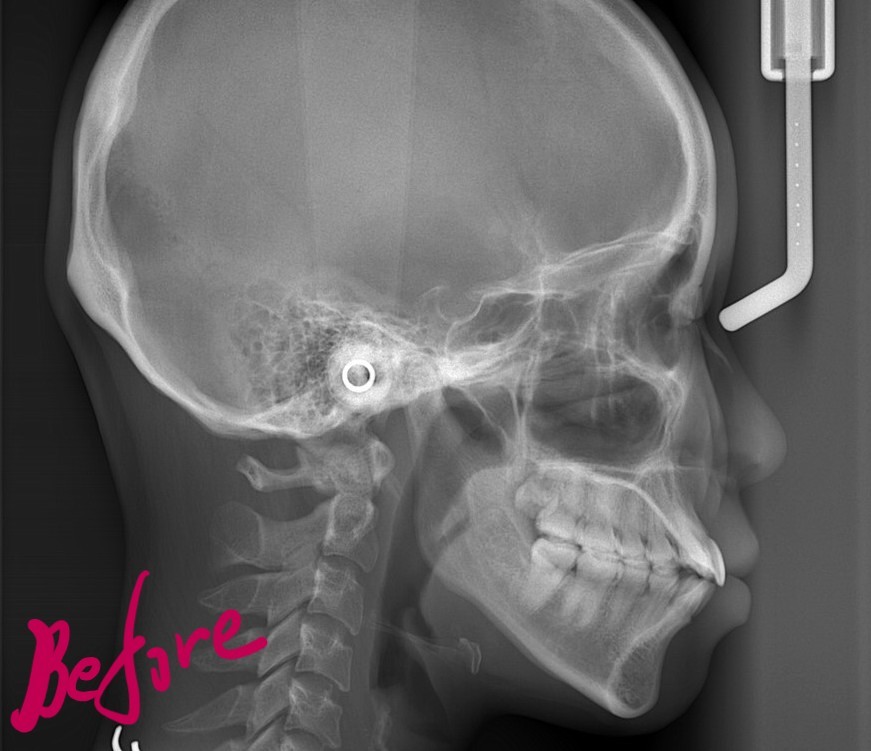

【Before】

【診断】

#1.歯と顎の不調和による叢生(軽~中等度)

と診断しました。

【治療方針】

1.上下左右の奥歯を1本ずつ抜歯してスペースを作り、前歯の乱れを改善

2.残りのスペース分を使い、上下前歯を可及的に後方へ移動

という治療計画にて、矯正を進めることにしました。

【抜歯】

上下の左右の奥歯を1本ずつ計4本抜歯(すべて前から4番目の第一小臼歯を抜きました)

左上の埋伏している智歯は治療開始後早期に抜歯します。

レントゲン写真でも比較してみましょう

左側が矯正治療前、右側が矯正治療後